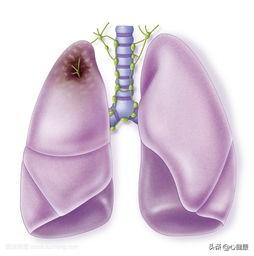

先ほど、胸が締め付けられるような症状は一般的であると言いましたが、気管支炎、喘息、肺水腫、肺塞栓症、胸水、気胸、脊髄由来の疾患などが引き金になることがあります。病気のない人でも、感情的・精神的な変化によって胸が締め付けられることがある。 これは神経学的な要因の役割によるもので、患者は最近のストレスや長期の安静不足によって神経障害を患い、その結果、対応する血管が痙攣性収縮を起こし、血液と酸素の正常な供給に影響を及ぼすことがあり、血管内にプラークが形成されるのではなく、血管の全体的な変化によって引き起こされることがある。前者の場合、実際に原因となる病変がないため、長引く傾向があり、患者は自己調節の後に回復することができる。後者の場合、病変が治療されない限り、患者は回復することはなく、時間とともに状態は徐々に悪化し、生命を脅かすことになる。

肺疾患や胸部疾患は、胸部圧迫感、喉頭、気管、太い気管支の炎症、腫瘍や異物、気胸、胸水、喘息、慢性閉塞性肺疾患、肺水腫、びまん性肺線維症、広範な実質病変、腫瘍、サルコイドーシス、肺無気肺、肺塞栓症などの原因となります。では、胸部X線検査や胸部CT検査を受け、呼吸器内科を受診する理由はあるのでしょうか?

3.心臓以外の病気慢性閉塞性肺疾患などの肺疾患や反射性食道炎などの消化器疾患も胸部圧迫感を引き起こすことがあり、心筋虚血の臨床的証拠がない場合は、他の全身疾患の可能性に注意する。

また、あなた自身が肺の病気を持っている場合、胸が合わなくなることがあります。

これには、気管支炎、肺炎、びまん性間質性肺疾患、胸水貯留、自然気胸、広範な胸膜癒着などの肺の最も一般的な呼吸器系疾患、重度の貧血、メトヘモグロビン血症などの血液系疾患、亜硝酸塩中毒や一酸化炭素中毒、不安や抑うつなどの精神医学的要因が含まれ、これらすべてが胸部圧迫感を引き起こす可能性がある。

4.肺疾患

通常、肺は全身に酸素を供給する役割を担っているが、肺に病変があれば酸素の供給が低下するため、胸が締め付けられるような痛みが生じる。

2.呼吸器系の疾患

呼吸器系も胸部にあり、呼吸器系に病気があると胸が締め付けられるような症状が現れる。例えば、肺がんでは気管支が閉塞し、胸が締め付けられるような息切れが起こります。例えば、高齢者の慢性肺気腫による心臓病でも胸のつかえが現れます。多量の胸水が肺を圧迫する場合にも胸が締め付けられることがあります。

最後に、肺疾患による胸部圧迫感の症状を明らかにする必要がある。